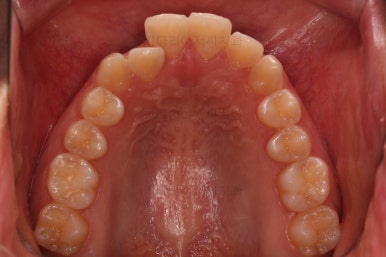

치열이 매우 바르게 되었고 교합도 양호하며 뻗쳐 있던 앞니 각도도 좋아졌네요.

돌출의 느낌도 처음보다 많이 좋아졌어요.

웃을 때 보이는 치열의 느낌도 좋고요.

전후 사진을 비교해 볼게요.

입술의 두께로 인한 돌출감 개선에 약간은 한계가 있었지만 그래도 본인이 만족한 수준에서는 돌출감을 개선했고 치열도 매우 가지런하게 마무리를 할 수 있었답니다.